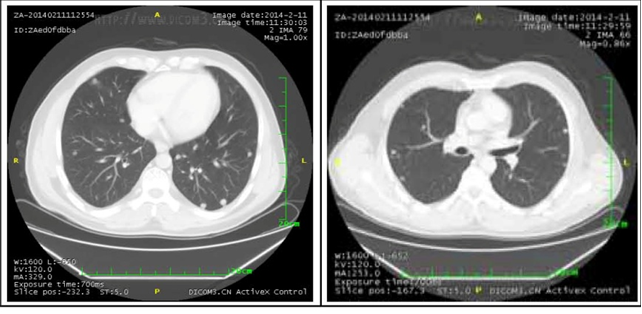

2. 肺部病灶治疗前后核磁对比:

肺部转移病灶在用药后2个月明显缩小,4个月后病灶基本消失。

治疗前

治疗2个月

治疗4个月

治疗6个月

治疗16个月